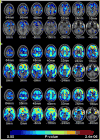

A central issue in cognitive neuroscience of aging research is pinpointing precise neural mechanisms that determine cognitive outcome in late adulthood as well as identifying early markers of less successful cognitive aging. One promising biomarker is beta amyloid (Abeta) deposition. Several new radiotracers have been developed that bind to fibrillar Abeta providing sensitive estimates of amyloid deposition in various brain regions. Abeta imaging has been primarily used to study patients with Alzheimer's Disease (AD) and individuals with Mild Cognitive Impairment (MCI); however, there is now building data on Abeta deposition in healthy controls that suggest at least 20% and perhaps as much as a third of healthy older adults show significant deposition. Considerable evidence suggests amyloid deposition precedes declines in cognition and may be the initiator in a cascade of events that indirectly leads to age-related cognitive decline. We review studies of Abeta deposition imaging in AD, MCI, and normal adults, its cognitive consequences, and the role of genetic risk and cognitive reserve.